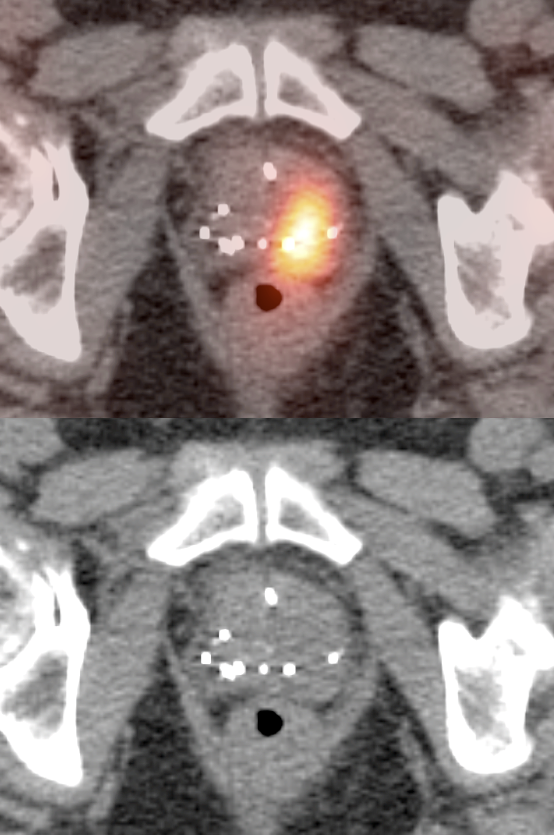

- Uptake associated with a visible lesion or area of focal calcification the CT exam.

- Focal uptake located in the peripheral zone.

- The presence of associated hypermetabolic nodes or bone lesions.

- Primary Lesion: Often not identified. When present, usually appears as a focus of intense uptake in the peripheral zone (MRI is superior in the evaluation of the primary lesion).

- Regional Disease: Usually hypermetabolic pelvic lymph nodes.